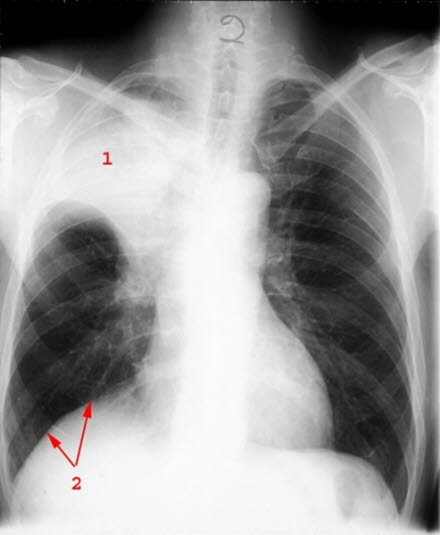

Småcellet anaplastisk carcinom

Atelektase av overlapp høyre lunge (1) på grunn av svulst som klemmer av bronkier

- Atelektase (sammenfall)

- Opptrekt mellomgolv (diafragma) pga atelektasen øverst i høyre lunge